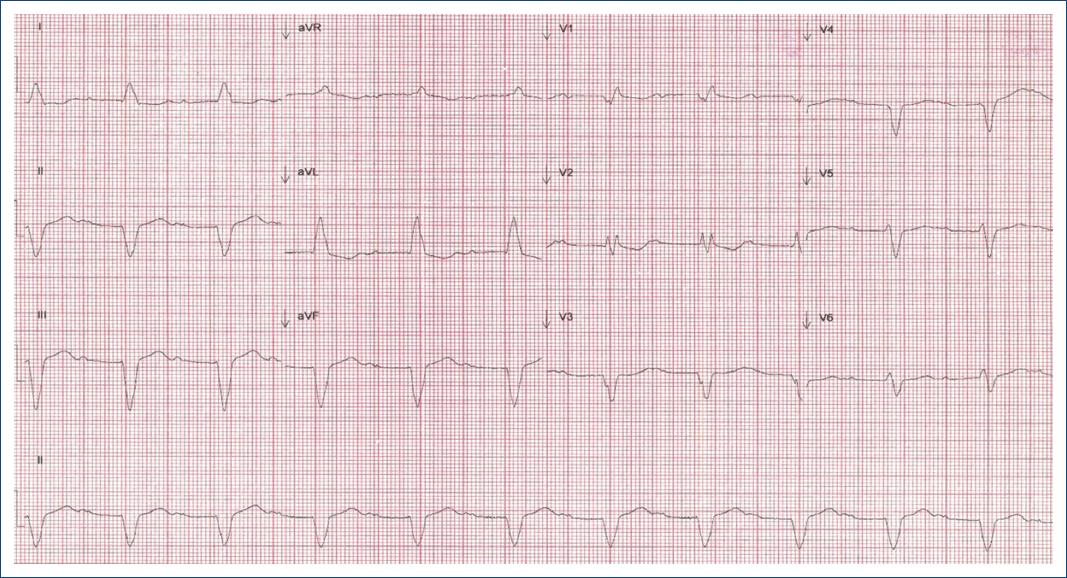

El electrocardiograma (ECG) basal (Fig. 1) en ritmo sinusal con bloqueo AV de 1.er grado con intervalo PR de 400 ms, frecuencia cardiaca (FC) 66 lpm, eje eléctrico del QRS 60°, QRS 200 ms, BRDHH y BFA.

Figura 1 Electrocardiograma previo a la estimulación hisiana. Ritmo sinusal con bloqueo atrioventricular de 1.er grado con intervalo PR de 400 ms, frecuencia cardiaca 66 lpm, eje eléctrico del QRS 60°, QRS 200 ms, bloqueo de rama derecha del haz de His y bloqueo del fascículo anterior.